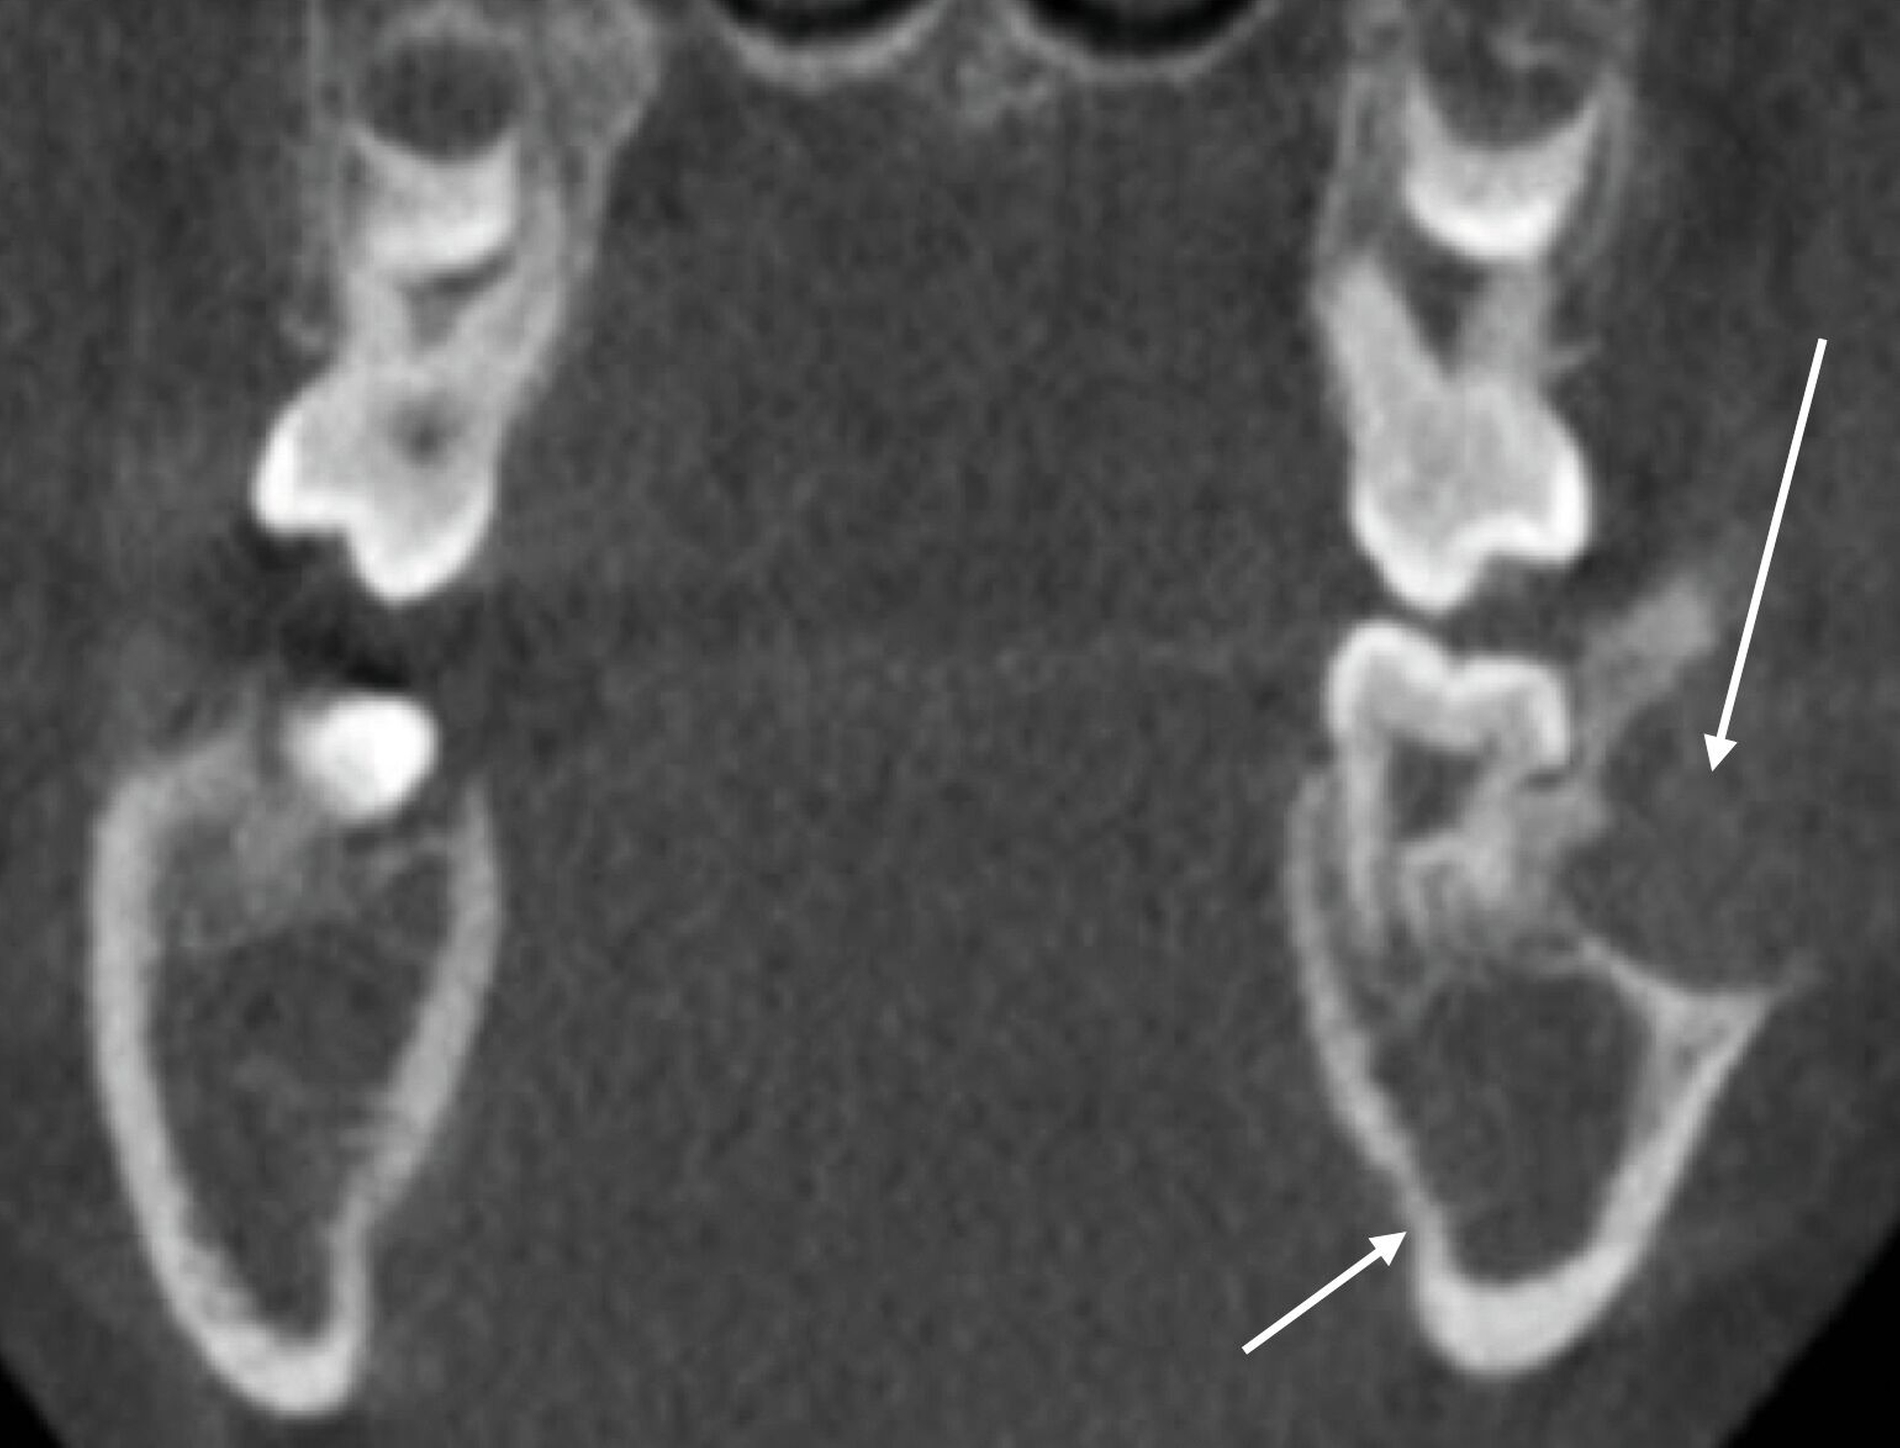

Zur weiteren Diagnostik wurde eine Panoramaschichtaufnahme durchgeführt. In dieser war ein radioluzenter, mehrkammeriger, scharf begrenzter Befund im Bereich des linken Unterkiefers um den retinierten Zahn 38 darstellbar. Auch auf der Gegenseite war eine, hier eher unklar begrenzte, Radioluzenz um den retinierten und verlagerten Zahn 48 zu erkennen (Abbildung 2).

Um diese Befunde bezüglich ihrer Lage und ihrer Ausdehnung genauer zu charakterisieren, erfolgte anschließend eine dreidimensionale Aufnahme in Form einer Digitalen Volumentomografie. In dieser ließen sich analog zu den Befunden in der zweidimensionalen Bildgebung gelappte hypodense Raumforderungen darstellen. Der sklerotische Randsaum und die – im Vergleich zur Spongiosa – hypodensere Struktur des Befunds im dritten Quadranten waren klar zu erkennen (Abbildung 3).

In der radiologischen Bildgebung findet sich – wie im vorgestellten Fall – ein unscharf begrenzter, teilweise polyzystischer Befund, der differenzialdiagnostisch von einem Ameloblastom und der Keratozyste unterschieden werden muss. Makroskopisch zeigt der Befund ein fleischfarbenes, rötlich-braunes, hämorrhagisches Erscheinungsbild. Der histopathologische Befund ist gekennzeichnet durch eine Proliferation mononukleärer Spindelzellen und mehrkerniger Riesenzellen. Die Raumforderung kann lobuliert und von Osteoid und Geflechtknochen umgeben sein [Gundlach, 2022]. Radiologisch und histologisch ist die Differenzialdiagnostik zu anderen riesenzellhaltigen tumorähnlichen und tumorösen Kieferveränderungen nicht immer einfach.